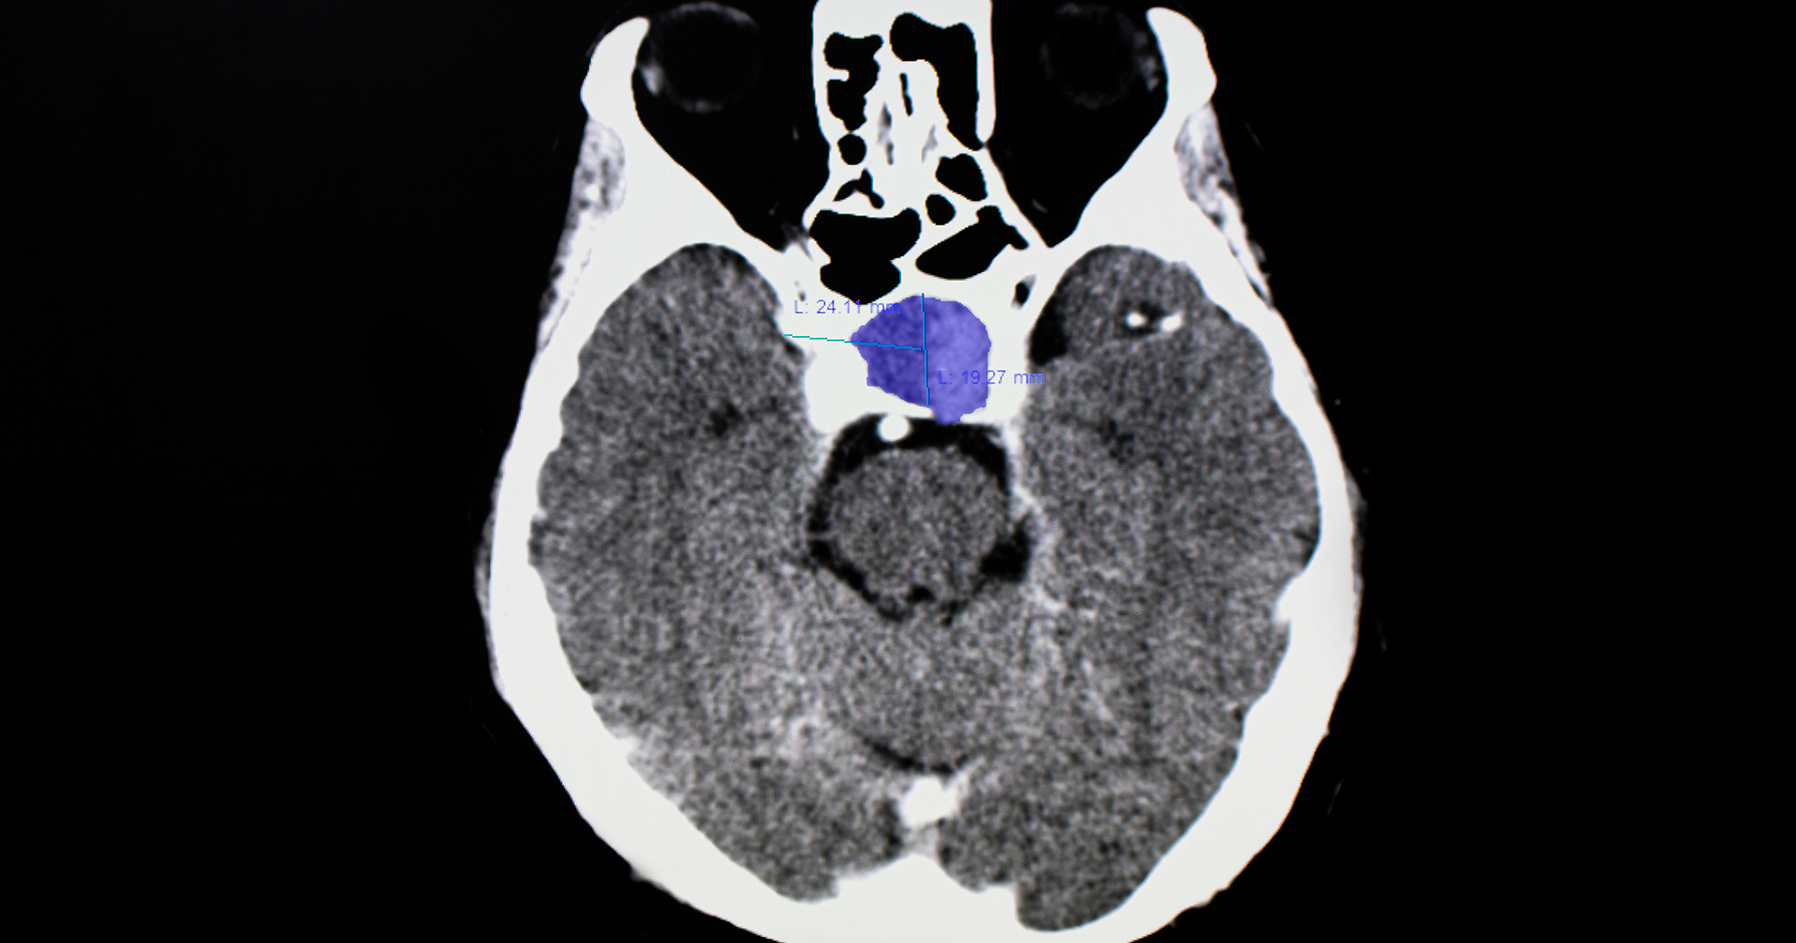

Image of a pituitary tumor in human body.

After evaluating your symptoms, your doctor will order blood tests to measure hormone levels. Your doctor will also order an MRI (magnetic resonance imaging) scan to look at the pituitary and other structures around it. If a pituitary tumor is found, more blood tests will be done to find out what type of tumor it is. Your doctor needs to know the type of tumor to plan treatment. Testing may also be needed to see if the tumor is affecting your vision.

After evaluating your symptoms, your doctor will order blood tests to measure hormone levels. Your doctor will also order an MRI (magnetic resonance imaging) scan to look at the pituitary and other structures around it. If a pituitary tumor is found, more blood tests will be done to find out if your tumor is making too much of a specific hormone. Your doctor needs to know the type of tumor to plan treatment. Testing may also be needed to see if the tumor is affecting your vision.